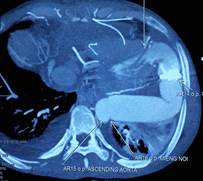

Nguyên tắc cơ bản của điều trị suy tim đó là điều trị căn nguyên gây suy tim nếu có thể làm được. Ví dụ: nếu do hở hay hẹp van tim thì có thể mổ thay hoặc sửa van tim. Tuy vậy, nhiều trường hợp không hề tìm thấy...